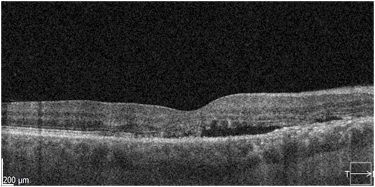

2. Fotokogulacja laserowa (LPC) miejsca przecieku. Przez kilka dekad LPC była podstawową forma leczenia CSCR. Warunkiem bezpiecznego zastosowania tej metody była i jest bezpieczna lokalizacja miejsca przecieku – w odpowiedniej odległości od centrum dołka. Dodatkowo, przeciek powinien być zlokalizowany, punktowy, a nie rozlany lub trudny do zidentyfikowania, jak to obserwujemy w niektórych przewlekłych postaciach CSCR. Zasady wykonywania LPC w CSCR sformułował Gass w latach 70-tych ubiegłego stulecia. Ze względu na uszkadzający charakter terapii zalecano najpierw obserwację przez kilka miesięcy. LPC stosowana była w przypadkach nieresorbującego się przecieku oraz w postaciach nawrotowych. Współcześnie LPC nadal jest stosowana, chociaż częściej terapię rozpoczyna się od laseroterapii podprogowej, n.p. SML. LPC jest dobrym rozwiązaniem w przypadku braku reakcji na SML. Jak wspomniano wcześniej, do wykonania LPC konieczne jest aktualne badanie angiograficzne (FA).

Stan po klasycznej fotokoagulacji laserowej siatkówki. Pacjent po wielokrotnej laseroterapii mikropulsowej – bez resorpcji płynu podsiatkówkowego. Wykonano ponownie FA i wykonano ogniskową laseroterapie na podstawie wyniku badania (zaznaczony okrąg). W SOCT widoczna całkowita resorpcja plynu, ale również znaczne ścieńczenie siatkówki.